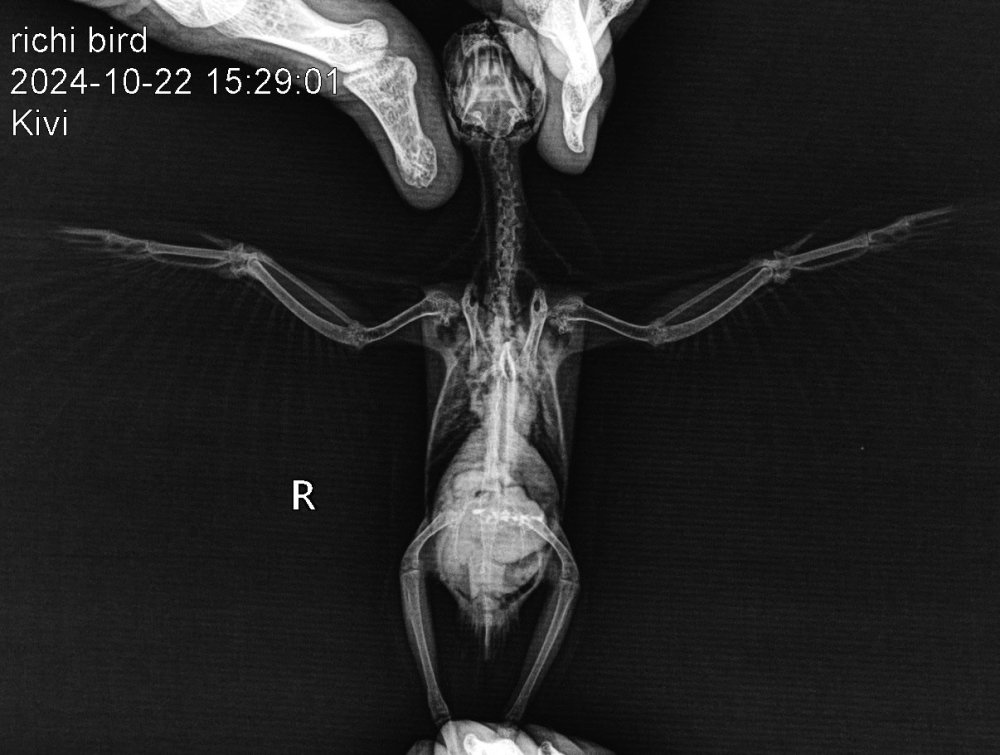

ДианаРикки Опубликовано 23 октября, 2024 #1 Опубликовано 23 октября, 2024 Вчера были на приеме у орнитолога, в Тбилиси. К сожалению, сказали очень печальный прогноз. Вес птицы всего лишь 28 грамм, критический. Сделали рентген, узи. Обнаружили кистообразную опухоль, начало подагры. Прикреплю вам файлы. И диагноз врача. Если вам не сложно, ознакомьтесь, пожалуйста. Сказали только обезбаливать анальгином. Больше никакого лечения. Даже предлагали усыпить, так как птица может испытывать боли, но рука не поднялась. Скажите, пожалуйста, насколько верен диагноз и настолько ли все плачевно или есть какие-то альтернативные варианты лечения? И можно что-то попробовать. Птица клюет шелушит зерна, но не ест. Пытаемся насильно кормить кашей. Отправили домой доживать свои дни. Не назначили никакого лечения, так как вес птицы очень мал. Также сказали не кормить насильно. Но я все де думаю, что опускать руки еще рано и может как-то можно набрать вес, чтобы провести лечение. Ведь подагру можно поддерживать , пока она не распространилась на органы. С каждым днем птице становится хуже. Прикрепляю диагноз врача и снимки рентгена. Спасибо